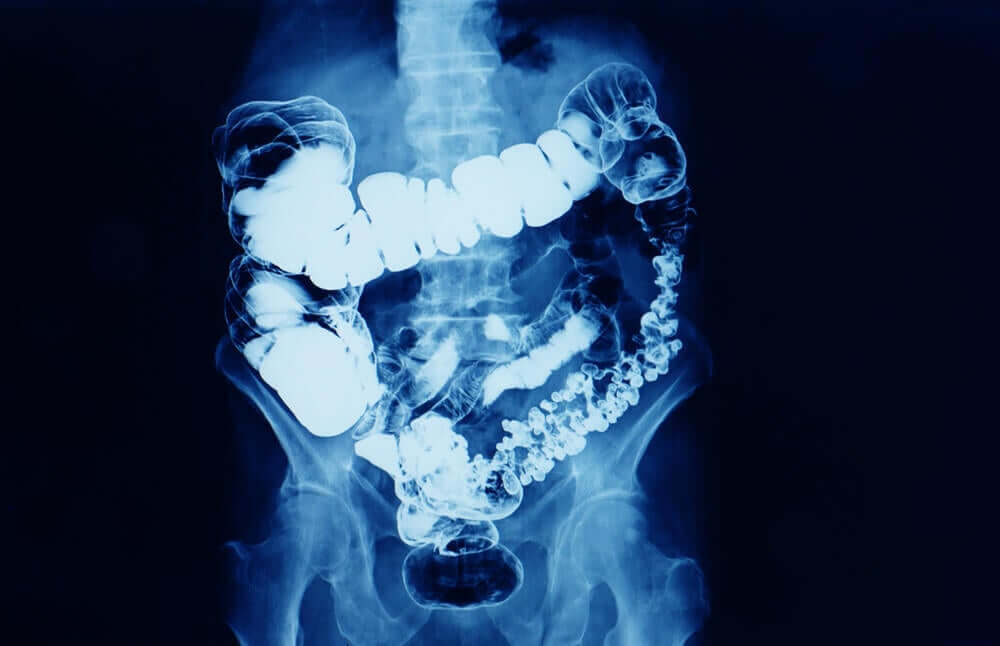

Światowy Dzień Walki z Rakiem Okrężnicy przypomina o chorobie onkologicznej, która rozwija się w jelicie grubym i odbytnicy. Termin rak jelita grubego jest również sposobem na określenie tej lokalizacji.

Jelito grube i odbytnica to ostatnia część przewodu pokarmowego po jelicie cienkim. W tym miejscu powstają odchody, które zostaną wydalone z organizmu niosącego odpady. Bolus pokarmowy jest odwadniany w jelicie grubym i przechowywany w odbytnicy w celu wydalenia.

Drugim badaniem i głównym zalecanym podczas Światowego Dnia Walki z Rakiem jest kolonoskopia. W tym badaniu lekarze pod sedacją wprowadzają endoskop – elastyczną rurkę z kamerą – do odbytnicy i jelita grubego. Obserwują na żywo prawdopodobnie dotkniętą błonę śluzową, mogą pobrać próbki do biopsji, a nawet usunąć polip, jeśli zostanie wykryty podczas badania.